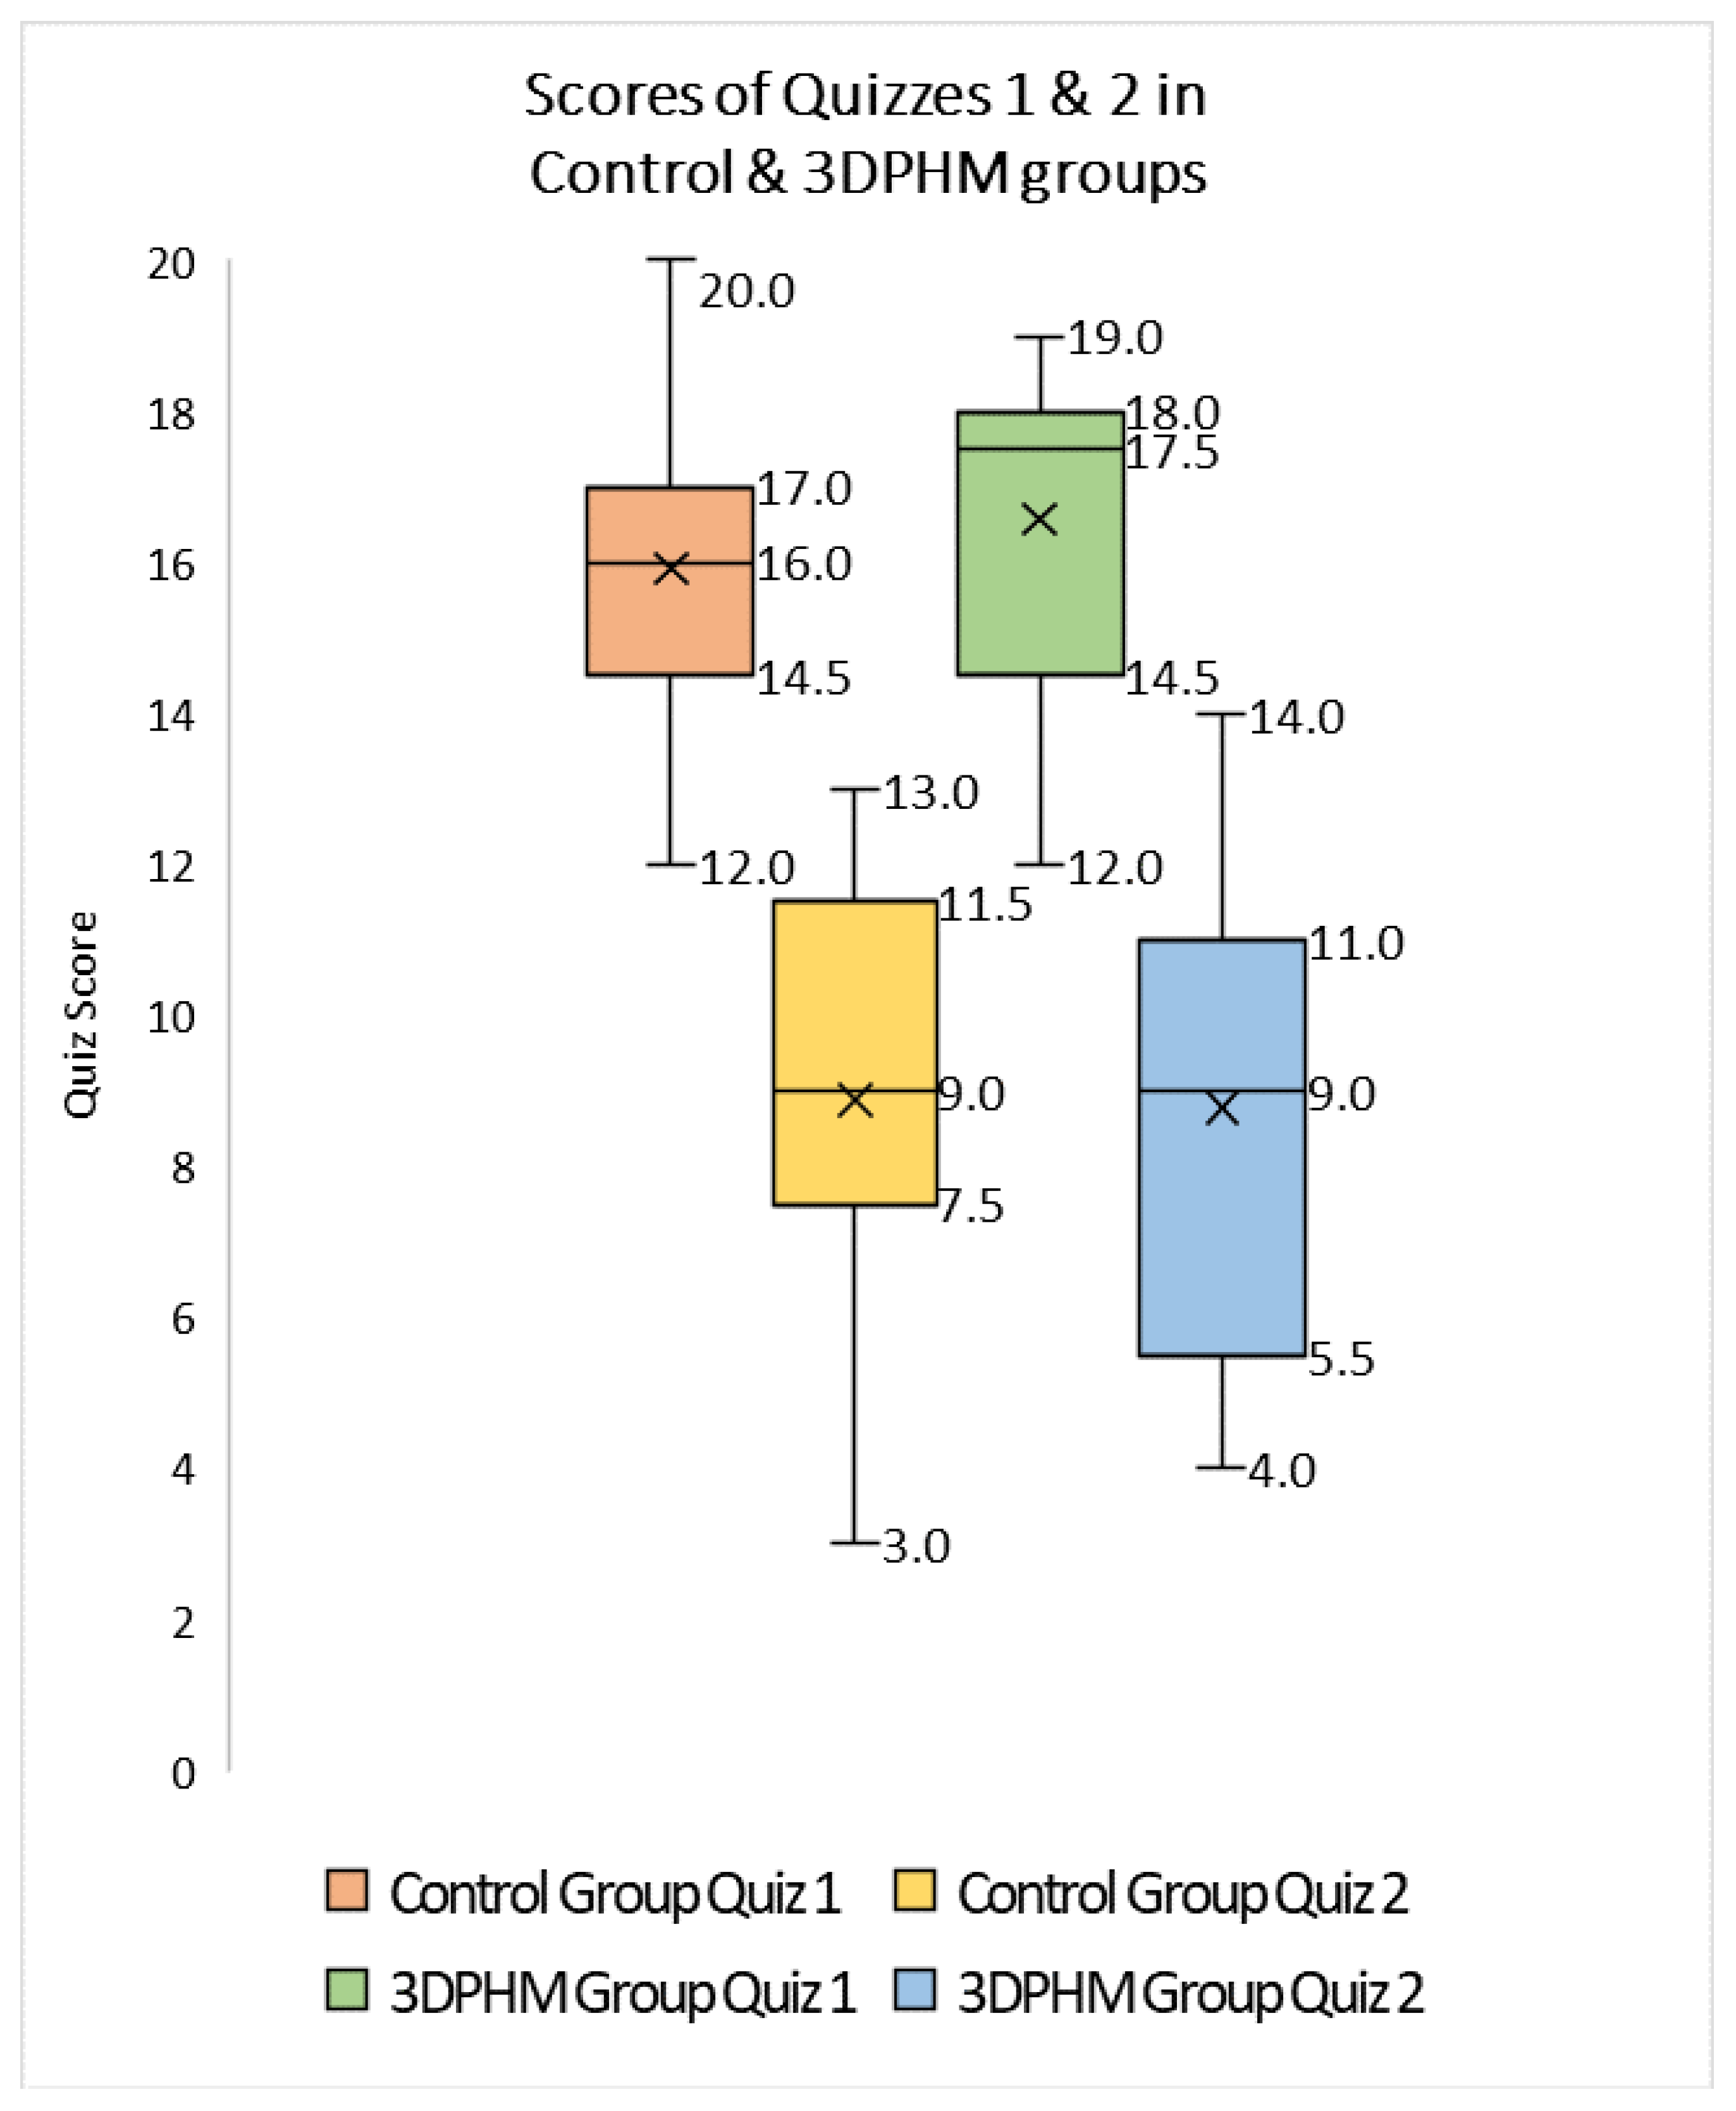

4.2. 3D-Printed CHD Models in Medical Education

- Lau, I.; Sun, Z. The role of 3D printed heart models in immediate and long-term knowledge retention in medical education. Rev. Cardiovasc. Med. 2022, 23, 022. [Google Scholar] [CrossRef]